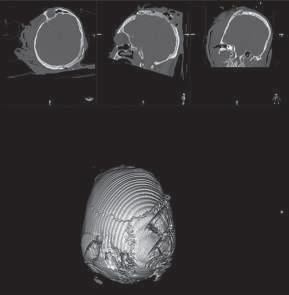

Lesões Ósseas

Palavras-chave: fraturas ósseas.

Keywords: bone fractures.

Introdução

O esqueleto do corpo humano é constituído por 206 ossos que são responsáveis pelas mais diversas funções, nomea damente: proteção dos órgãos internos, suporte mecânico, regulação da homeostasia mineral, funções hematopoiéti cas. Ao contrário dos outros tecidos no corpo humano que após lesão regeneram com tecido cicatricial, o tecido ósseo regenera com osso novo, indistinguível do osso original.

Devido à sua elevada área de exposição, o esqueleto apre senta, frequentemente, sinais de traumatismos, advindo daí a sua importância numa perspectiva médico-legal, quer em termos de patologia, quer de clínica forense. Após uma le são óssea, há a formação de um hematoma e uma resposta inflamatória que vai induzir a formação de osso novo por osteoblastos locais. Há a constituição de uma matriz co lagenosa e a diferenciação de células mesenquimatosas, com a formação de cartilagem. Os condrócitos proliferam, hipertrofiam e segregam fatores que vão induzir a ossifi cação da cartilagem, com a conversão de cartilagem em osso novo – ossificação endocondral. Este osso é remode lado pela ação combinada de osteoblastos e osteoclastos, dando origem a osso maduro de acordo com as linhas de stress/tensão (Clohisy et al., 2009). Dependendo do timing da lesão óssea, assim, poderemos ter lesões ante mortem, peri mortem e post mortem.

A presença de um calo ósseo, denotando assim um osso que teve tempo para maturar, aponta para uma lesão ante mortem. Já uma lesão que não apresenta sinais de conso lidação pode ter tido origem peri mortem ou post mortem A constituição do osso é alterada após a morte, com perda de água e da sua elasticidade, tornando assim o osso mais quebradiço, o que vai influenciar as características das lesões ósseas post mortem

Nas lesões peri mortem, encontra-se uma coloração mais uniforme e a presença de fraturas incompletas, em espiral e de tensão-compressão, frequentemente mais oblíquas. Nas lesões post mortem, em que o osso se encontra mais seco por desidratação, a coloração pode ser mais heterogénea

(por exposição ao meio envolvente), as superfícies de fratu ra vão apresentar-se mais regulares, com bordos retos, e as fraturas serão mais longitudinais e transversais irregulares (Cunha & Pinheiro, 2005/2006).

A forma e a aparência das lesões ósseas podem refletir não só a direção, a área, a velocidade, a massa e a forma do objeto produtor da lesão, mas também as próprias ca racterísticas inatas do tecido ósseo, como o seu conteú do mineral, as características físicas do osso em questão ou eventuais alterações patológicas do mesmo (Cunha & Pinheiro, 2005/2006). Sendo uma combinação de matéria orgânica e inorgânica, o tecido ósseo é capaz de sofrer de formação elástica e plástica antes da falência. Mas uma vez iniciada a fratura, esta propagar-se-á através do osso até que a energia seja dissipada.

Existem três tipos principais de lesões: cortantes, contun dentes e perfurantes. Quando há uma combinação destas, podemos ter lesões mistas, como as perfuro-contundentes provocadas por projéteis de armas de fogo. Por regra, os diferentes tipos de lesões apresentam características típi cas dos instrumentos responsáveis pelas mesmas, apesar de o mesmo instrumento poder ser responsável por diferen tes tipos de lesões e a mesma lesão poder ser provocada por instrumentos diferentes.

36.1

Lesões cortantes e corto-contundentes

As lesões provocadas por instrumentos cortantes vão de pender das características da sua lâmina, o que pode per mitir identificar o instrumento responsável pelas mesmas. É possível a análise da impressão provocada no osso – dos entalhes ósseos e dos seus bordos, paredes e pavimen tos – e identificar padrões nas estrias que permitam dis tinguir o tipo de instrumento. A análise das estrias através da microscopia eletrónica permite identificar imperfeições específicas das lâminas, o que pode levar à identificação do instrumento específico responsável por uma determi nada lesão. A partir da análise das lesões, pode ser ainda

© PACTOR 473

36

possível identificar a direção do movimento e os padrões de corte (Bartelink et al., 2001; Ciallella et al., 2002; Saville et al., 2007; Symes, 1992; Symes et al., 2001).

Assim, podemos encontrar lesões produzidas por instru mentos de gume liso, serrilhado ou complexo, simples ou duplo. Quando além da ação do gume o instrumento apre senta um peso elevado, vamos ter lesões de características mistas (corto-contundentes), como acontece com lesões

provocadas por machados, espadas ou catanas (Figura 36.1), que atuam pela ação do peso e do gume cortante (Humphrey & Hutchinson, 2001; Lewis, 2008).

As lesões ósseas do tipo cortante ou corto-contundente ocorrem em grande número no contexto de acidentes de trabalho com trauma dos membros superiores, nomeada mente das mãos (Figura 36.2).

Fig. 36.1 Lesão por catana

Fig. 36.2 Lesão por serra